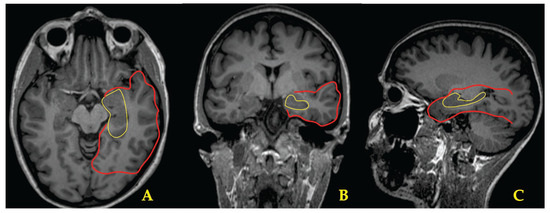

2.2. MRI

| Patient’s N/Age/Gender | Age at Seizure Onset | Seizure Semiology | EEG Interictal | EEG Ictal with Scalp Electrode Placement | MRI Eloquent Area/Side | Neuro-Psychology/Area/Side | Concordance of the Modalities | Side and Area of Performed Surgery | Early Post-Surgery Period | Outcome | Follow Up (Months) |

| 1/28/Male | 6 | Focal—with fear, impaired consciousness and oral automatisms | Bi-Temporal | L-anterior Temporal (F7–F9) | L-HS | L-Medial Temporal | +(−)+++ | L-Hippo-campectomy (AASJ15) | One FBTCS 3rd month after surgery | Engel 1a | 16 |

| 2/40/Female | 20 | Focal—preserved consciousness, with pressure in head and heating | L-Temporal | L-anterior (F7–F9) and middle (T7–T9) Temporal | L-HS | Bi-Frontal, R-Parietal | ++++(−) | L-Hippo-campectomy (AASJ15) | _ | Engel 1b | 5 |

| 3/42/Female | 9 | Focal—unpleasant sensation in the mesogastrium, with fear and impaired consciousness | Bi-Temporal | R-anterior (F8–F10) and middle (T8–T10) Temporal | R-HS | Bi-temporal | +(−)++(−) | R-Hippo-campectomy (AASJ15) | _ | Engel 1a | 9 |

| 4/43/Female | 27 | Focal—epigastric aura, tachycardia, impaired consciousness and oral automatisms | L-Temporal | L-anterior (F7–F9) and middle (T7–T9) Temporal | L-HS | Bi-Temporal | ++++(−) | L-Hippo-campectomy (AASJ15) | One FBTCS within 24 h of surgery | Engel 1a | 9 |

| 5/43/Male | 14 | Focal—with unpleasant taste, “uncooked beans”, tachycardia, inadequate speech; Impairment of consciousness, oral and manual automatisms, more prominent in the left hand. | L-Temporal | L-anterior Temporal (F7–F9) | L-VS | R-Temporal and Frontal | ++++(−) | L-Hippo-campectomy (AASJ15) | One FBTCS within 24 h of surgery | Engel 1a | 5 |

| 6/30/Male | 8 | Feeling of ringing in the ears, unexplained fear, impaired consciousness, deviation of the head and eyes to the left, oral and left manual automatisms, dystonia in the right hand, up to 1 min | L-Temporal | L-anterior (F7–F9) and middle (T7–T9) Temporal | L-HS L-Peri-ventricular Heterotopia | L-Temporal | +++++ | L-Hippo-campectomy (AASJ15) | _ | Engel 1a | 5 |